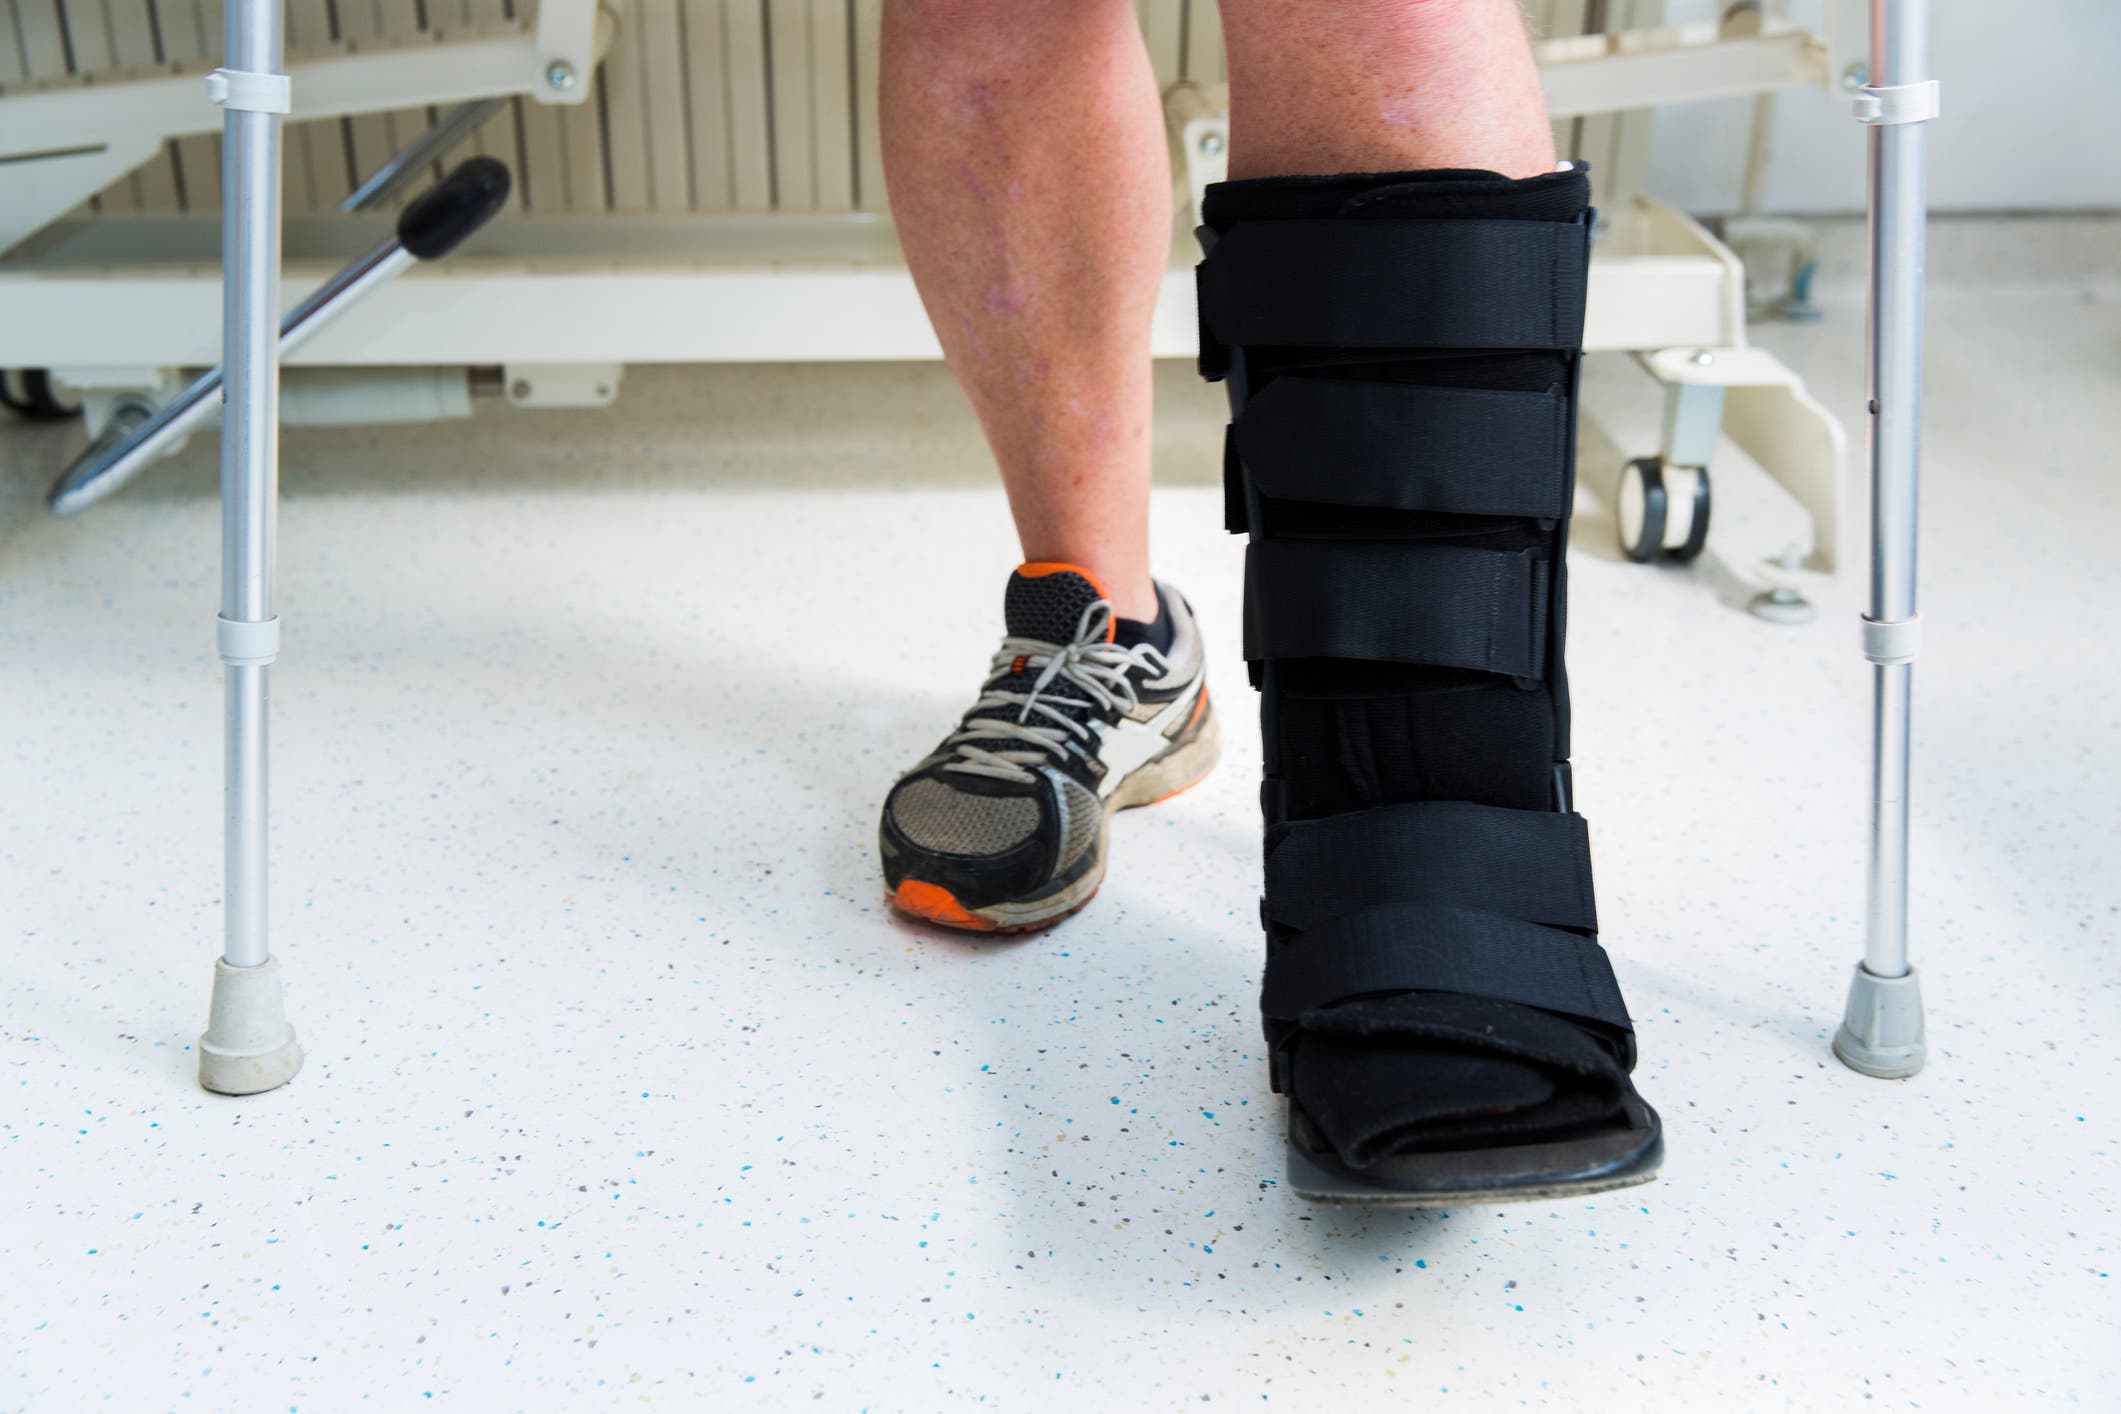

For moderate-risk injuries, or low-risk injuries at higher grades, biking may need to be limited, as it can still put strain on bones, despite the lack of impact, while water-based training (swimming, water running) can continue. In any case, pain should be used as a guide-increased pain during or after activity indicates too much bone loading for the stage of healing. High-risk fractures often put a full halt on training, though. Muscle tensions or any movement at the fracture site are risky, meaning that total rest is needed, likely including immobilization and/or non-weight bearing (hi, crutches!) on the affected limb.